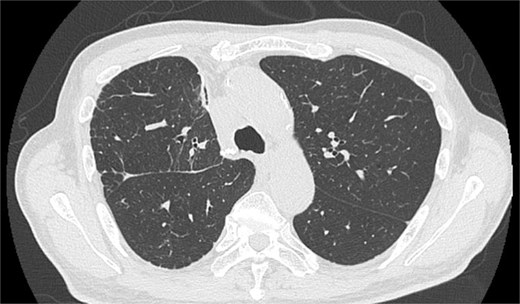

On POD 6, SE developed and spread to the chest, neck, and face. CT demonstrated remarkable mediastinal and SE with minimal lung collapse (Fig. 2; Video 2). Therefore, a chest tube was inserted, but minimal AL occurred from the chest tube, and the emphysema worsened. On POD 11, we performed thoracoscopic exploration and therapeutic intervention. Dense adhesion was confirmed between the staples on the interlobular plane and the dissected upper mediastinum. These were released, revealing the previous pleural tear. No other causative factors were observed. CT and operative findings suggested late-onset AL into the dissected mediastinum through dense adhesions. A leak test under positive pressure of up to 20 cmH2O revealed no AL from the pleural tear. The tear was sealed using a PGA sheet and fibrin glue, and 130 ml of autologous blood was injected into the pleural space to seal the dissected mediastinum and prevent air inflow (Video 3).

Image of postoperative mediastinal and SE with little lung collapse.

After the reoperation, AL was not observed, and SE regressed. The chest tube was removed on POD 5 after the reoperation (POD 16 after initial surgery). The patient was discharged on POD 18 after initial surgery. CT performed after 1 year revealed no emphysema or cancer recurrence (Fig. 3). The patient was informed of the complications and accepted the treatment outcomes.